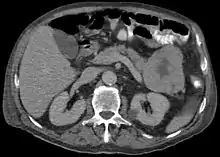

ACC are typically large, up to 10 cm, and soft compared to pancreatic adenocarcinoma, lacking its dense stroma. They can arise in any part of the pancreas.[2]

Histomorphologically, the tumour resembles the cells of the pancreatic acini and, typically, have moderate granular cytoplasm that stain with both PAS and PASD.[4]

Light microscopy of an acinar cell carcinoma biopsy typically shows granular appearance.[6] Immunohistochemistry is usually positive for trypsin, chymotrypsin and lipase.[6] On genetic testing, altered genes/proteins are typically found for p53, SMAD4, APC, ARID1A and GNAS.[6]